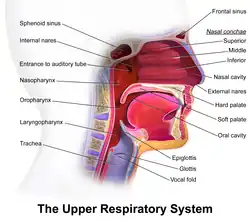

The superior conchae are smaller structures, connected to the middle conchae by nerve-endings, and serve to protect the olfactory bulb. The superior conchae attach to the ethmoid bone. The openings to the posterior ethmoidal sinuses exist under the superior meatus.[3] The sphenoid sinus ostium exists medial to the superior turbinate.[5]

The middle conchae are smaller but have the most complex anatomy of the nasal turbinates. They originate from the lateral edge of the cribriform plate of the ethmoid bone. They insert anteriorly into the frontal process of the maxilla and posteriorly into the perpendicular plate of the palatine bone.[6] There are three mutually perpendicular segments of the middle turbinate: from proximal to distal, there is the horizontal segment (axial plane), the basal lamella (coronal plane), and the vertical segment (sagittal plane). They project downwards over the openings of the maxillary and anterior and middle ethmoid sinuses, and act as buffers to protect the sinuses from coming in direct contact with pressurized nasal airflow. Most inhaled airflow travels between the inferior concha and the middle meatus.[3] In humans, they are usually as long as the little finger.

The conchae comprise most of the mucosal tissue of the nose and are required for functional respiration. They are enriched with airflow pressure and temperature-sensing nerve receptors (linked to the trigeminal nerve route, the fifth cranial nerve), allowing for tremendous erectile capabilities of nasal congestion and decongestion, in response to the weather conditions and changing needs of the body.[4] In addition, the erectile tissue undergoes an often unnoticed cycle of partial congestion and decongestion called the nasal cycle. The flow of blood to the nasal mucosa in particular the venous plexus of the conchae is regulated by the pterygopalatine ganglion and heats or cools the air in the nose.

The nasopulmonary and nasothoracic reflexes regulate the mechanism of breathing through deepening of inhalation. Triggered by the flow of the air, the pressure of the air in the nose, and the quality of the air, impulses from the nasal mucosa are transmitted by the trigeminal nerve to the breathing centres in the brainstem, and the generated response is transmitted to the bronchi, the intercostal muscles, and the diaphragm.